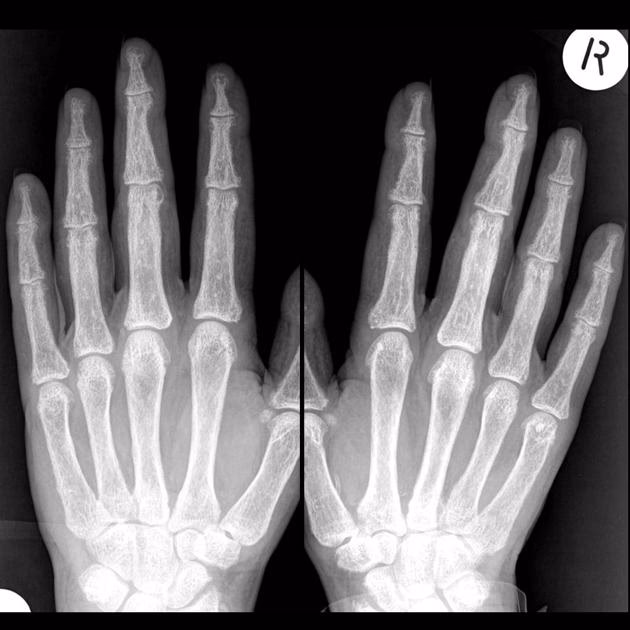

Thyroidea-Akropati: En Sjælden men Markant Komplikation

Ja, hypertyreose forårsaget af Graves' sygdom kan føre til akropati. Thyroidea-akropati er en meget sjælden manifestation, der forekommer hos mindre end 1% af patienter med Graves' sygdom. Den udvikler sig næsten udelukkende hos patienter, der allerede har alvorlig oftalmopati og dermopati. Akropati er karakteriseret ved tre primære træk:

- Clubbing: En fortykkelse og opsvulmning af de yderste led af fingre og tæer, hvilket får neglene til at krumme nedad som bagsiden af en ske.

- Bløddelshævelse: Hævelse af vævet i hænder og fødder, som kan give et hævet, "dejet" udseende.

- Periosteal knoglenydannelse: Radiologiske undersøgelser (røntgenbilleder) kan vise ny knogledannelse langs skaftet af knoglerne i hænder og fødder, hvilket giver et karakteristisk "sæbeboble"-lignende udseende.

Mekanismen bag akropati er ikke fuldt ud forstået, men den menes at være tæt forbundet med de ekstremt høje niveauer af TRAb-antistoffer, som ses hos disse patienter. Disse antistoffer stimulerer sandsynligvis ikke kun skjoldbruskkirtlen, men også bindevævsceller i hænder og fødder, hvilket fører til vækst og inflammation. Akropati udvikler sig typisk sent i sygdomsforløbet, ofte flere år efter den indledende diagnose af Graves' sygdom.